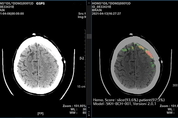

[엔트로피타임즈 민혜정 기자] SK㈜ C&C(사장 윤풍영)가 개발한 AI 뇌출혈 영상 의료 솔루션 ‘메디컬 인사이트 플러스 뇌출혈’의 효과성을 입증한 논문이 국제 학술 저널에 실렸다. 지난 3일, SK㈜ C&C가 이 논문이 네이처 파트너 저널인 ‘디지털 메디신’에 게재됐다고 통해 밝힌 것인데, ‘디지털 메디신(npj. Digital Medicine)’은 과학분야 세계적 권위지인 ‘네이처 리서치’의 인공지능의학 전문 저널로, 2018년 1월 출범 이후 네이처 파트너 저널 중 가장 영향력 있고 인기 있는 저널로 꼽히고 있다. 서울대학교병원 영상의학과 윤태진 교수와 아주대학교병원 영상의학과 최진욱 교수가 주 저자로 집필한 ‘딥러닝 기반의 뇌출혈 자동 탐지 알고리즘 : 무작위 확증 임상시험(Deep learning based automatic detection algorithm for acute intracranial haemorrhage: a pivotal randomized clinical trial)’ 논문에는 총 7명의 연구 교수진이 함께 했다. ‘메디컬 인사이트 플러스 뇌출혈’은 뇌 CT 영상을 수초 내로 분석해 출혈 위치와 이상 여부를 의료